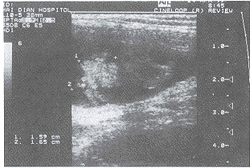

患者, 女性, 24岁, 未婚, 右腹股沟肿物3年余,平素无不适。近两年来每于月经前一周明显肿大, 伴疼痛, 5~6天后缓解。查体:右腹股沟区近阴阜处可见一9cm×6cm囊实性肿物,界限不清, 压痛(±), 不能还纳。右侧大阴唇无肿大, 外阴正常。B超示:右侧腹股沟区近阴阜处可见一9cm×6cm×2.3cm的无回声区,边界清晰, 内有密集细小均匀光点漂浮及部分不规则中等回声, 大者1.6cm×1.7cm(图1)。CDFI:中等回声内可探及低速动静脉血流信号,无回声区内及周边未见血流信号。盆腔扫查:子宫位于左下腹膀胱左后方近腹股沟处,形态大小回声未见异常, 左卵巢正常,右卵巢未探及。初步诊断:异位附件(右侧)不除外。子宫内膜异位症?手术切除后病理示为卵巢、卵管组织及少许平滑肌组织。

图1 右侧附件异位